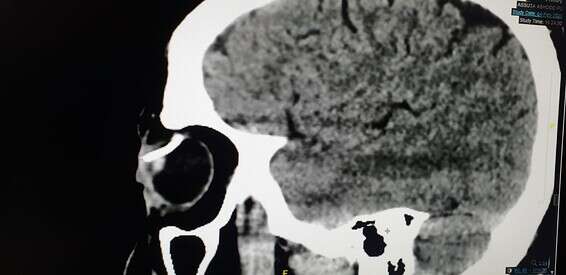

תשאול מהיר של המטופל העלה כי בזמן העבודה הוא הרכיב משקפי מגן לא אוטמות, ומעין "מסמר" חדר לתוך עינו. את קצה המסמר ניתן היה לראות בעין בלתי מזויינת, אך בבדיקת CT התברר כי המסמר חדר את גלגל העין והגיע עד לרשתית.

צילום: מח' עיניים בי"ח אסותא אשדוד